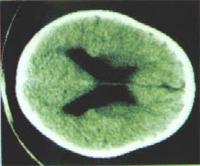

大腦皮質(cerebral cortex)是大腦的表層,由灰質構成,其厚度約為1到4mm,其下方大部分則由白質構成。大腦中間有一裂溝(大腦縱裂,longitudinal fissure),由前至後將大腦分為左右兩個半球,稱為大腦半球(cerebral hemisphere)。兩個半球之間,由胼胝體(corpus collosum)連線在一起,使兩半球的神經傳導得以互通。